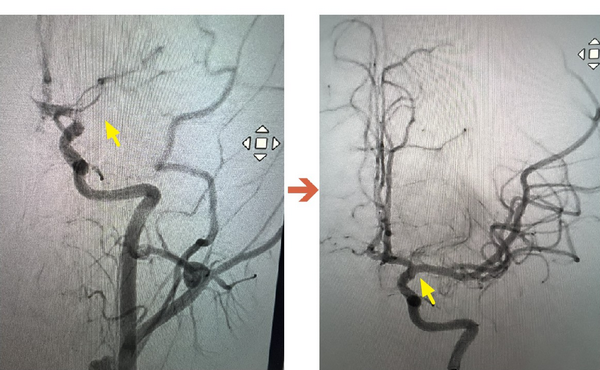

▲ICA血管攝影,圖左箭頭處為血栓阻塞血管。圖右箭頭處為已打通血管。(圖/聯新國際醫院提供)

在與家屬充分溝通後,影像醫學科主任暨取栓醫師郭葉璘隨即與取栓團隊進行急性腦中風顱內動脈血栓移除(Intra-arterial thrombectomy, IAT),並從腹股溝導引導管至左側中大腦動脈阻塞處,採用強力抽吸方式清除血栓。手術從開始到打通血管僅約10分鐘,成功取出4個血栓,最大達1.1公分。術後患者血流恢復暢通。